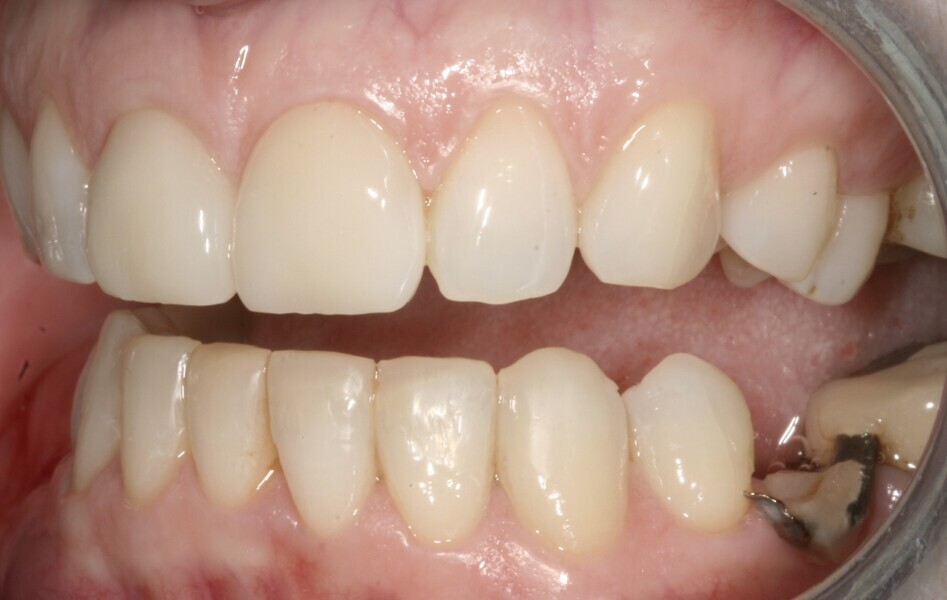

In 2021, the patient decided to have the two maxillary central incisor restorations replaced with a lithium disilicate crown and veneer (Fig. 13). The maxillary palatal platforms created with Venus Diamond in 2017 were still functional, and the repaired mandibular central incisal edge was still intact (Figs. 14 & 15). The original edge bonding on the other mandibular teeth still remained in place, 17 years later.

Fig. 14: 2021—the repaired mandibular central incisal edge still intact.

Fig. 15: 2021—the maxillary palatal platforms created with Venus Diamond still functional.